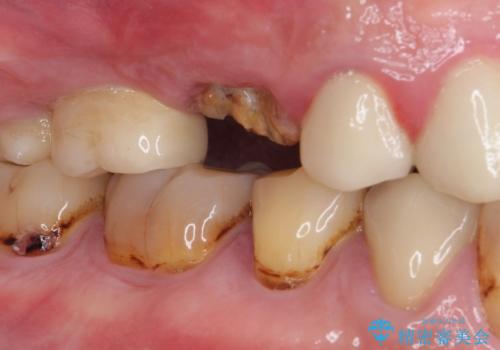

- 咬合力により歯が割れてしまった方のインプラント治療です。

抜歯後4ヶ月ほど待ち、後方のインプラントと同一メーカーのインプラントを埋入することとしました。